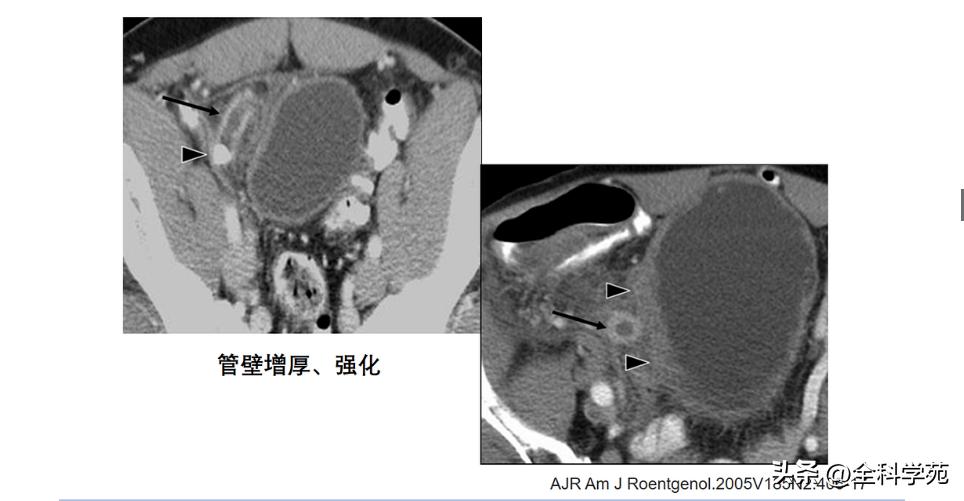

◆ 阑尾壁增厚

>3mm

CT: 阑尾壁明显增强

◆ 阑尾的内径增宽

> 10 mm

6-10 mm 伴阑尾壁增厚、壁明显强化,周围脂肪间隙模糊或分层(靶征或牛眼征,表明粘膜下水肿的液体含量vs 气体含量